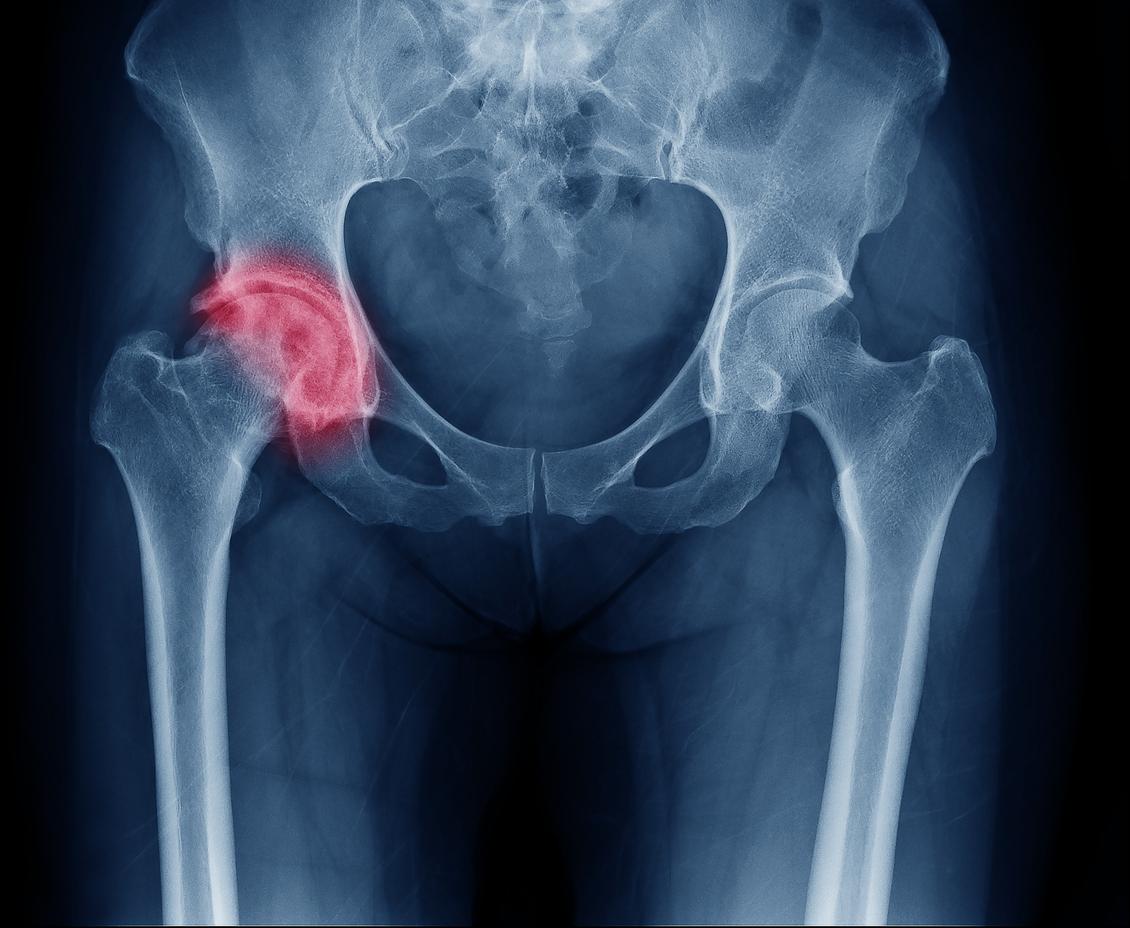

- En France, selon la Haute autorité de santé, l'incidence de fracture de hanche est d'environ 50 000 cas chez les femmes et 16 000 cas par an chez les hommes.

Ce n'est pas une raison pour abandonner fruits et légumes sur le bord de la route, mais d'après une étude publiée dans la revue BMC Médecine, les femmes adeptes du régime végétarien courent plus de risque de se fracturer la hanche en vieillissant que celles qui suivent une alimentation omnivore.

Résultat, au bout de deux décennies, 822 cas de fractures, soit un peu plus de 3%, ont été constatés parmi la cohorte de femmes. Et les végétariennes sont surreprésentées : chez elles, la probabilité de se blesser en vieillissant augmentait de 33% par rapport aux consommatrices régulières de viande et/ou de poisson.